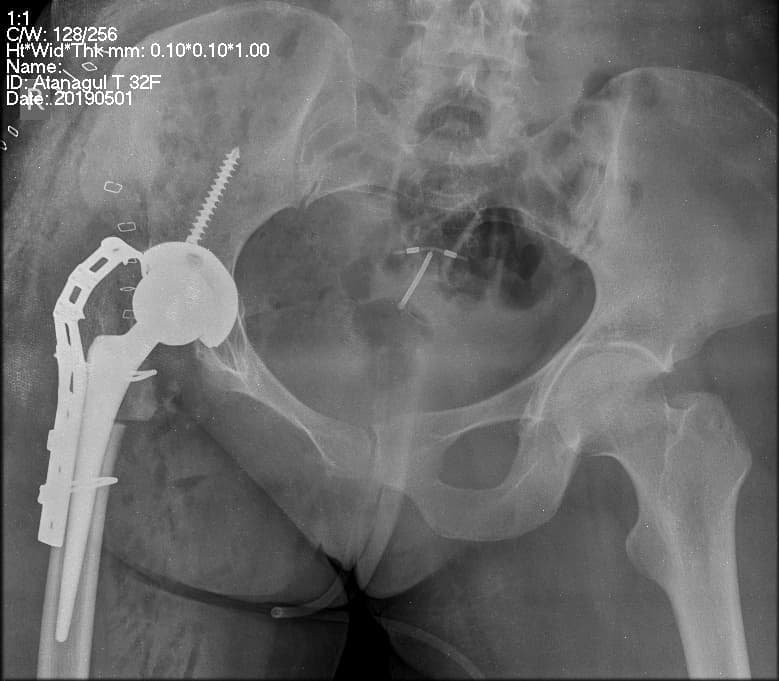

Мэс заслын өмнөх болон дараах рентген зураг

Дунд чөмөгний хүзүү болон их бага төвгөр хамарсан үений хугарал

Нас ахих тусам ясны чанар муудаж сийрэгжилт ихэсдэг мөн түнхний үений анатомийн бүтцээс /дунд чөмөгний хүзүүний хатуу яс нимгэн, ууттай шингэн дотор байрладаг, цусан хангамж муу/ зэргээс шалтгаалан жижиг гэмтлийн улмаас түнх хүзүү хэсгээр болон их бага төвгөрөөр хугарах нь маш элбэг. Дээрхи ясны сийрэгжил, анатомийн бүтцийн онцлогоос шалтгаалсан түнхний хүзүүний хугарал нь бороололт муу, бороолсон ч эргэн үхжих магадлал их тул 60 дээш насныханд ихэвчилэн түнхний үеийг хагас болон бүрэн солих мөн шургаар бэхлэх мэс заслыг хийнэ.